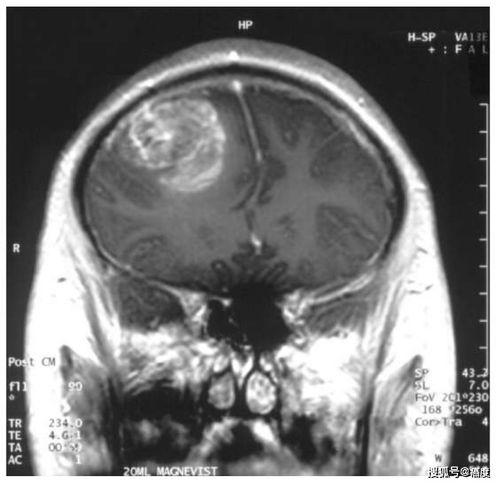

在关于脑瘤的讨论中,一种特殊的情形引起了我们的关注:恶性脑瘤的转移及其可能对肠胃的影响。

让我们聚焦在恶性脑瘤,如胶质母细胞瘤。理论上,这类肿瘤有可能通过血液循环转移至肠胃,但在实际的临床案例中,这种情况极为罕见。通常,这种转移发生在疾病进展的晚期,可能会引发一系列肠胃症状,如腹痛、腹泻,甚至可能出现便血。值得注意的是,脑肿瘤的主要转移路径通常是沿神经轴向周围组织扩散,转移到远处器官的概率相对较低。